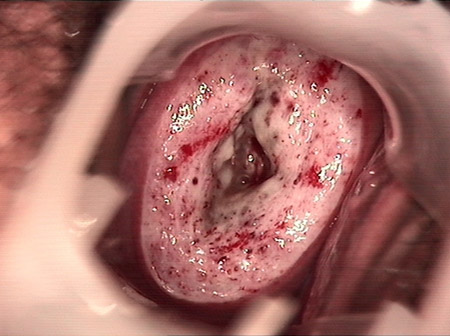

婦科leep錐切手術(shù) CIN2-3

CIN 2-3

CIN 2-3 碘著色后

CIN 2-3 leep術(shù)后

CIN 2-3 修復(fù)后

CIN 2-3 修復(fù)后(圖2)